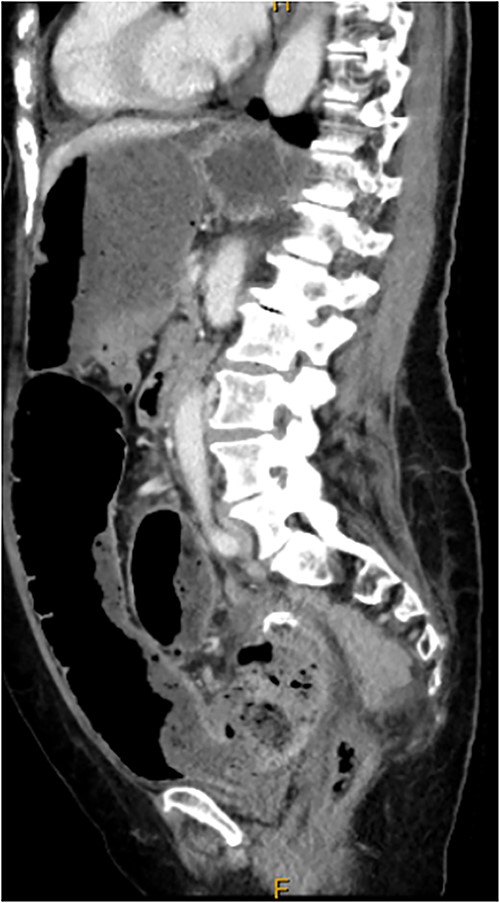

Computed tomography on current presentation demonstrated a mechanical LBO with a transition point at the anastomosis, with significant large bowel dilatation (see Figs 1 and 2). Flexible sigmoidoscopy revealed severe luminal narrowing at the anastomosis 20 cm from the anal verge prohibiting scope progression, with intra-luminal purulent discharge. She underwent a laparotomy and Hartmann’s procedure, with findings of severe colorectal anastomotic stenosis and a small, localized perforation. The colon proximal to the stricture was dilated but viable, with a caecal diameter of approximately 20 cm (see Figs 3 and 4). Histopathology confirmed a benign stricture with extensive fibrosis and a segment of full thickness necrosis and perforation. There was no evidence of malignancy and the post-operative recovery was unremarkable.

CT scan demonstrating stricture at site of sigmoid anastomosis and proximal dilatation and faecal loading.